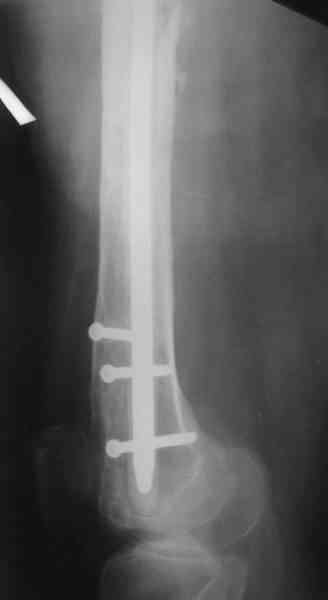

В настоящее время наш пациент ( см. http://weborto.net/forum/1177351385/) ходит с одним костылем. У него периодически открывается свищ на задне-наружной поверхности бедра с умеренным серозно-гнойным отделяемым. Температура тела и анализы нормальные. На рентгенограммах имеются признаки консолидации ложного сустава.

Иллюстрации:

1, 2, 3, 4 - рентгенограммы бедра от 8 августа этого года (через четыре месяца после операции);